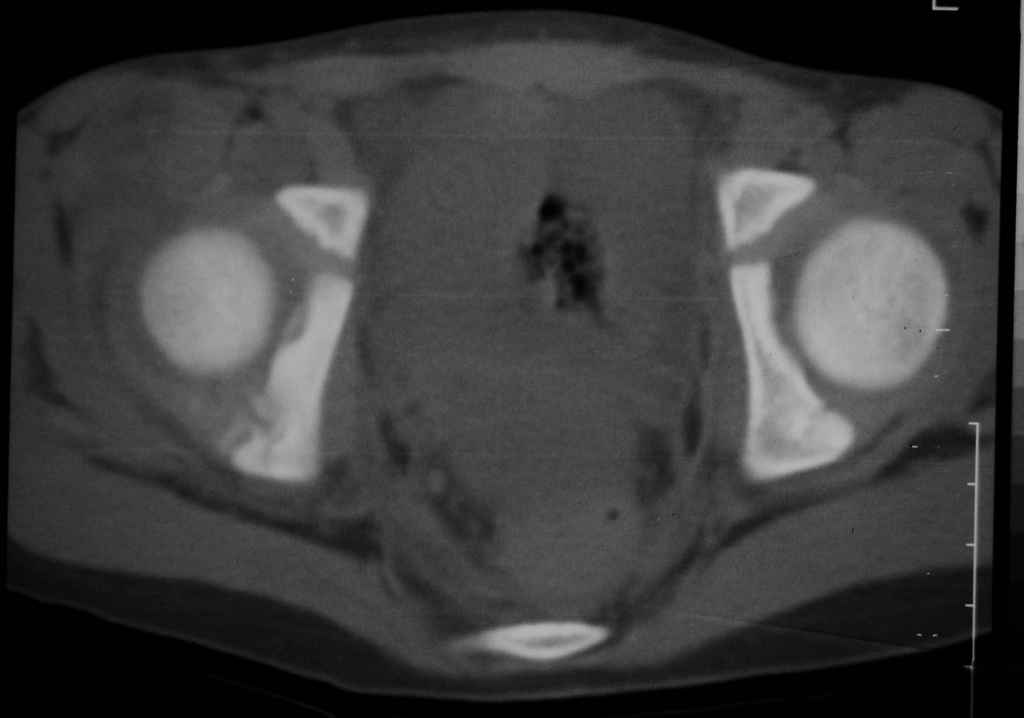

Уважаемые коллеги, помогите определиться с тактикой лечения. Ребёнок 7 лет, травма 11.09.08, поступил с травматическим вывихом бедренной кости.

Вывих вправлен, конечность фиксирована на скелетном вытяжении. Что делать с переломом подвздошной кости? Лечить консерватино или оперировать?